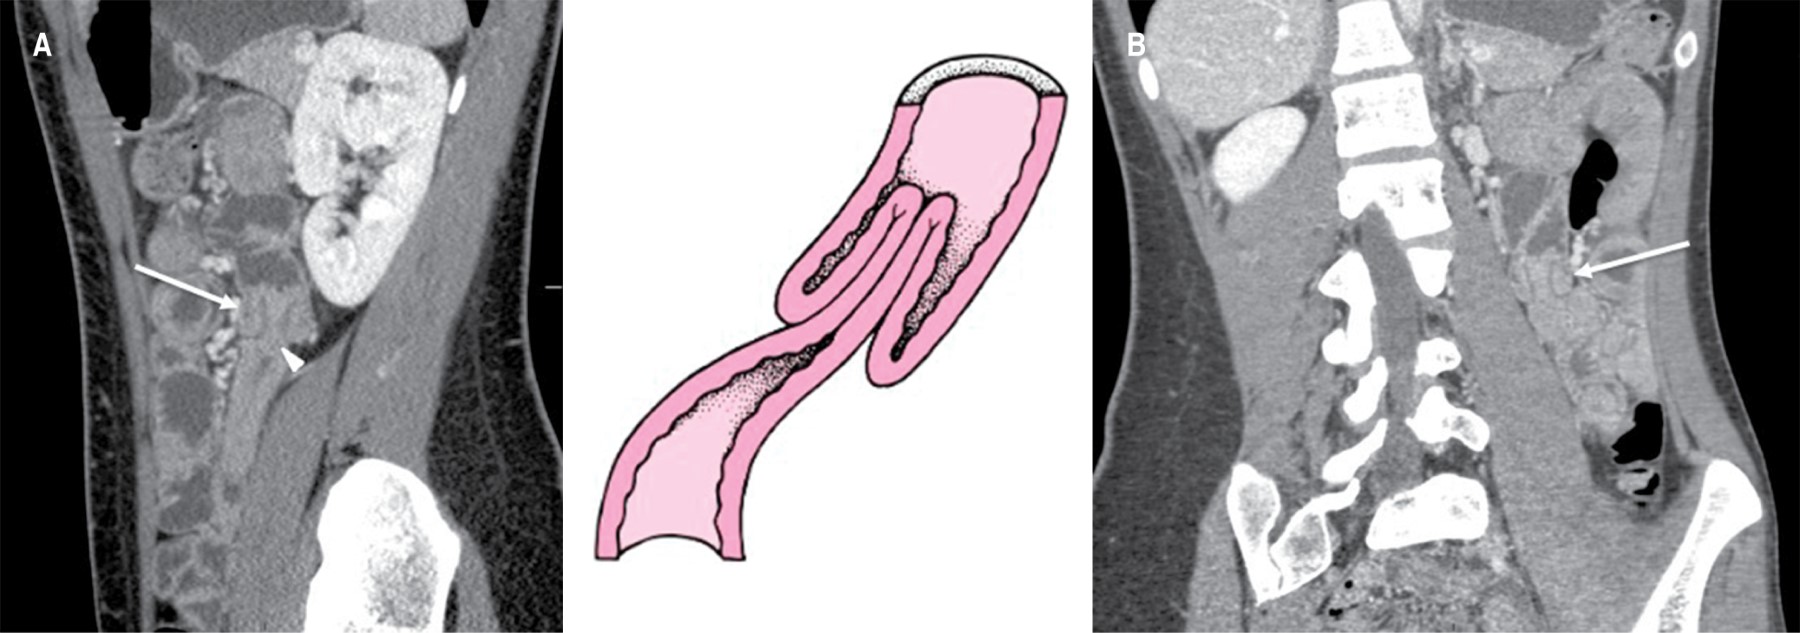

Ante la duda diagnóstica, se solicitó una tomografía con contraste intravenoso. Se reportó poca cantidad de líquido libre intraabdominal y discreto engrosamiento generalizado de las paredes intestinales sin datos de obstrucción o perforación de tubo digestivo. En el corte axial, a nivel del flanco izquierdo y en la topografía del yeyuno, se observó una imagen en "signo de diana" o "tiro al blanco" (Figura 1) misma que, en las imágenes de reconstrucción sagital y coronal, corroboró un deslizamiento de 2.3 cm de intestino invaginado dentro de sí mismo (Figura 2A y B), dando como resultado un diagnóstico compatible con intususcepción yeyuno-yeyunal.5

Figura 2